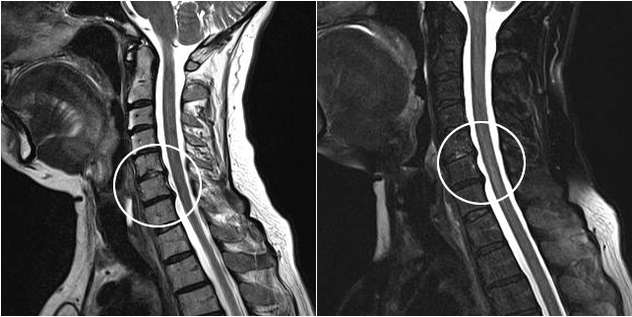

Do nowoczesnych metod diagnostycznych zalicza się MRI i CT, które pozwalają najdokładniej zbadać procesy niszczenia tkanki chrzęstnej i kostnej. Ponadto za pomocą tej techniki można wygodnie diagnozować przepukliny i inne wady tkanek miękkich w pobliżu źródła choroby.